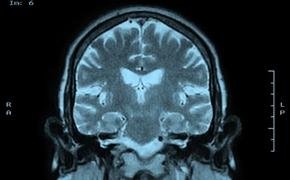

연구진은 봉사활동자들의 뇌를 MRI로 스캔했고 슬하전두대상피질(subgenual anterior cingulate cortex) 부분이 활성화된 것을 발견했다. 또한 이들의 특징을 찾았다. 타인에게 이익이 되는 행동양식을 빨리 배우고 반대로 자기 이익을 위한 행동은 늦게 배운다는 점이다.

연구를 이끈 파트리시아 락우드(Patricia Lockwood) 박사는 “슬하전두대상피질 활성화 정도는 사람마다 다르다”며 “동정심 수준이 높은 사람은 그렇지 않은 사람보다 활동 속도가 빠르다”고 말했다. 이어 “사회적 행동을 배우는 것이 뇌의 특정부분과 연결됐고 이는 동정심과도 연결 가능성이 있다”고 밝혔다.